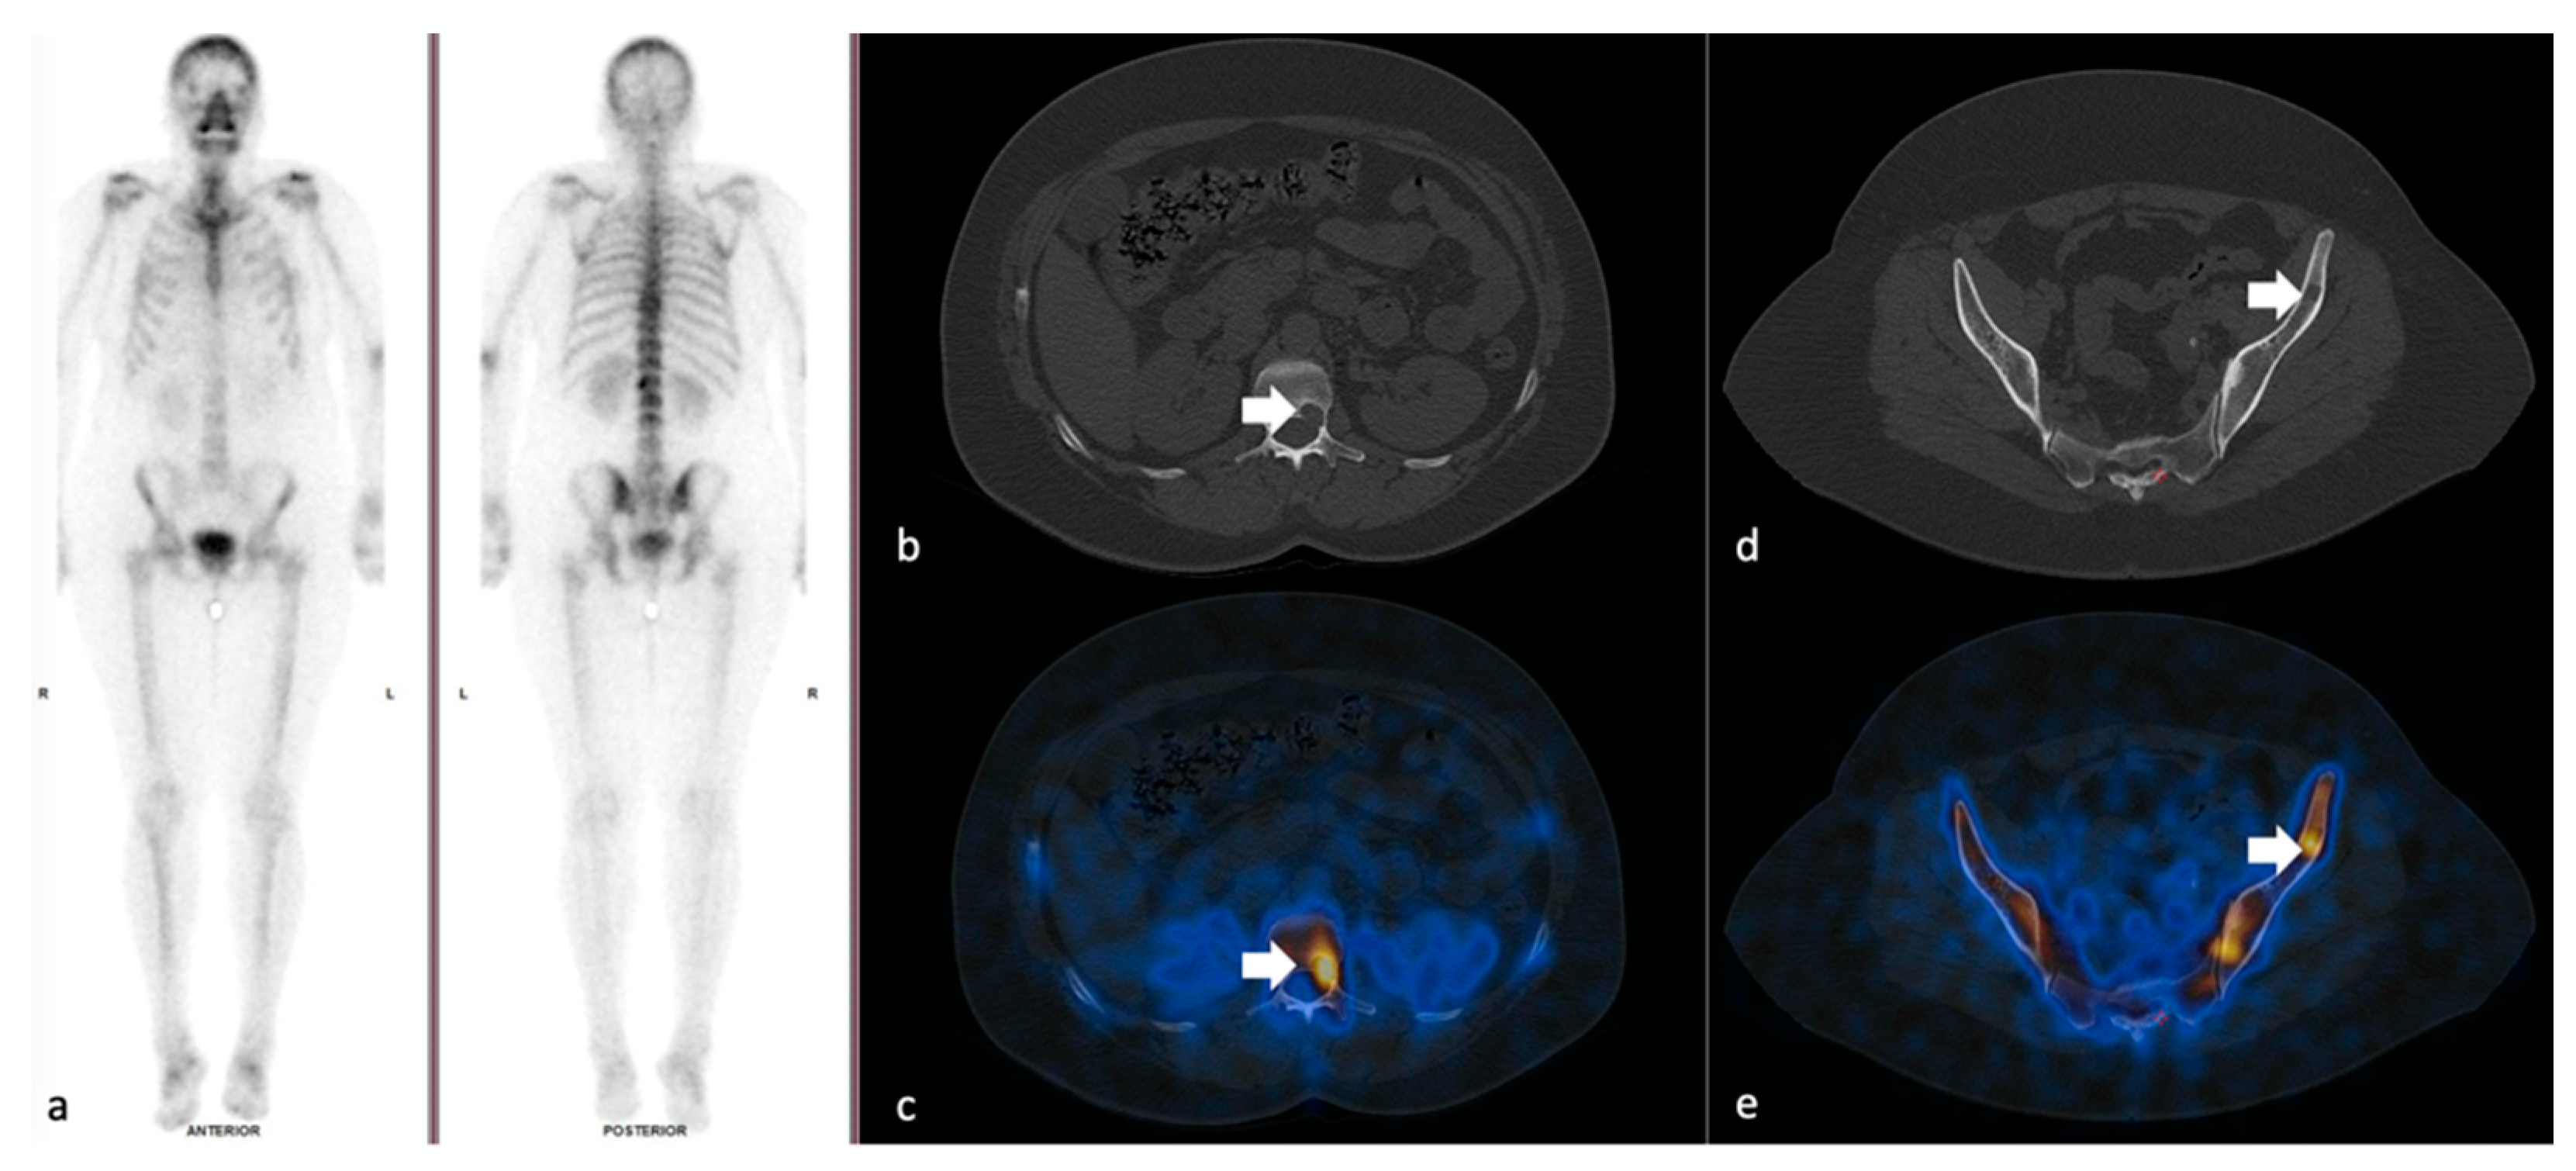

3.2. SPECT-CT SUVmax in Metastatic Lesions and Degenerative Bone Disease

3.3. SUVmax Cutt-off Value in Differentiating between Degenerative and Metastatic Lesions

3.4. SUVmax Overlapping